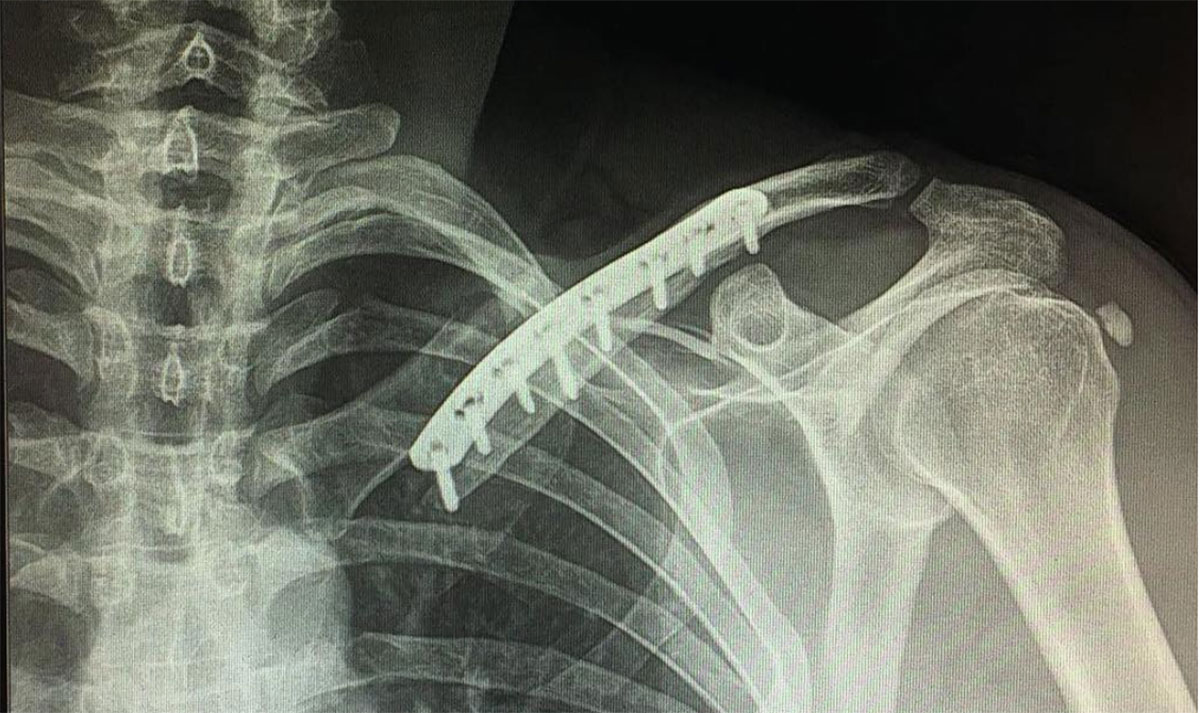

Strijbos also posted a picture from hospital this week of his broken collarbone. It’s not yet known when either rider will be fit to ride again or whether the squad will draft in replacements.